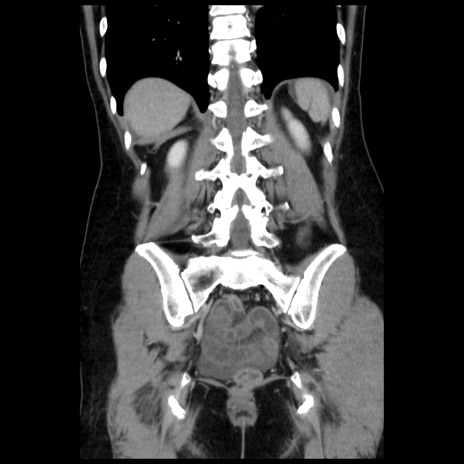

横断像

【症例】 50歳代女性

【主訴】 腹痛

【現病歴】前日生レバーを食べた。今朝に排便あり。 昼前に突然発症の腹痛を生じ、当院救急外来を受診した。

【既往歴】 子宮筋腫にてで子宮全摘後

【身体所見】 意識清明、腹部:平坦、軟、下腹部やや左を中心に圧痛・反跳痛あり、筋性防御あり

【データ】WBC 7800、CRP 0.07